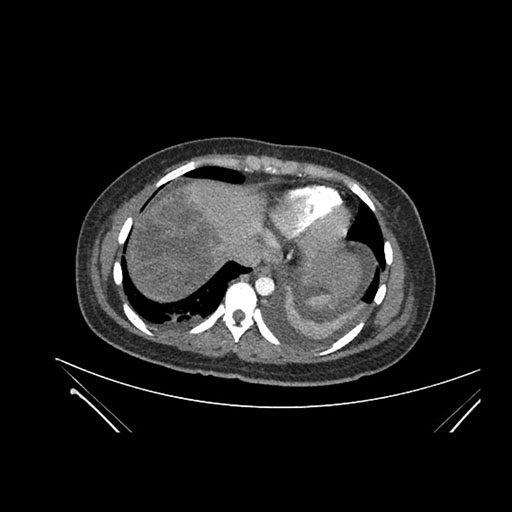

Imaging Analysis

Look through the patient's CT scan to identify any areas of concern for the necessary procedure.

Axial Venous

Based on initial findings, which issue(s) would you be most concerned about?